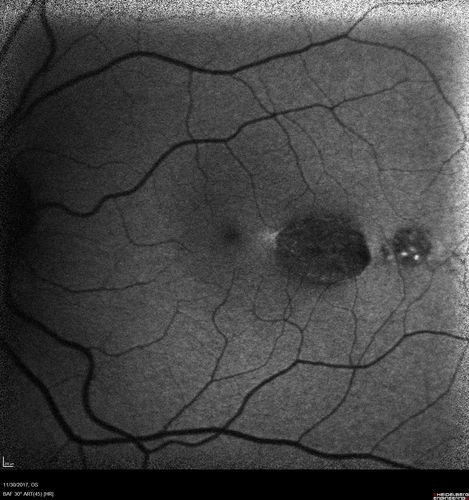

Torpedo Maculopathy

Likely a variant of CHRPE